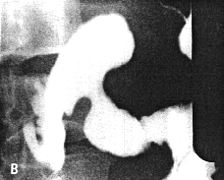

Case 33.7 M.B., 68 year old female, presented with a large, hard epigastric mass. Radiology showed a constant narrowing of the distal 3.0 to 4.0 cm of the stomach, somewhat resembling partial contraction or spasm of the pyloric sphincteric cylinder (Fig. 33.7A). However, it contained a filling defect and mucosal folds were absent. While some degree of movement was seen, this was atypical, with total absence of cylical contraction and relaxation of the cylinder (Fig. 33.7B - E). The base of the duodenal bulb appeared normal. Emptying of barium suspension was not significantly delayed.

At Billroth II partial gastrectomy a large, ulcerated pyloric carcinoma, extending aborally as far as the pyloric ring, was removed. The duodenum appeared normal. Microscopy revealed a signet ring cell carcinoma extending as far as the lamina propria and not involving the muscularis. The duodenum was confirmed to be normal.

![]() |

| Fig. 33.7. A Case M.B. Narrowing distal 3.0 to 4.0 cm of stomach resembling partial contraction or spasm of sphincteric cylinder. |

![]() | |

| Fig. 33.7 B-E. Case M.B. Filling defect in narrowed region. Mucosal folds absent. Some movement evident but cyclical contraction and relaxation of sphincteric cylinder absent. Base of duodenal bulb appears normal. | |